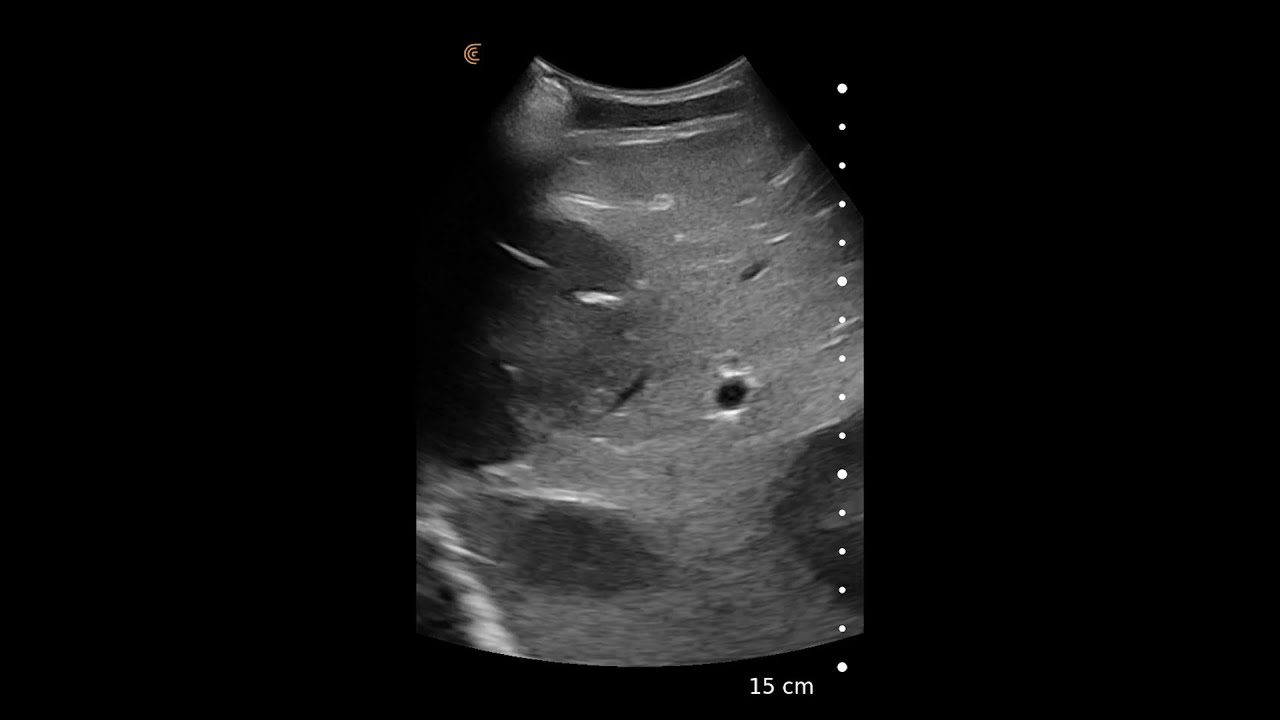

From clarius.com

Liver Metastases Clarius Does Liver Mets Cause Pain In most cases, there is no way to cure liver metastases. Cancer in the liver can cause different symptoms based on how much of the liver is involved. There may be no symptoms in the early stages of liver metastasis. Many of these symptoms are very common and can be caused by different conditions. The symptoms of metastatic liver cancer. Does Liver Mets Cause Pain.